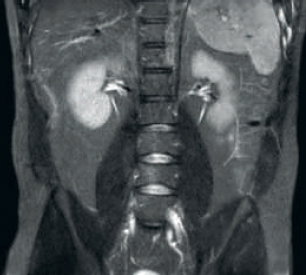

Mayor consistencia y mejor calidad de imagen La tecnología de recepción de RF dStream digitaliza la señal del RM directamente en la bobina de radiofrecuencia, lo que resulta en un aumento de hasta un 40 % más de la SNR* en todo el volumen de la imagen. Flujo de trabajo simplificado y rendimiento mejorado La bobina posterior integrada en la mesa elimina el manejo de la bobina en el 60 % de los exámenes. Las ligeras bobinas anteriores conformadas y las conexiones de bobina de un solo cable y de una sola mano contribuyen a la facilidad operativa.

El Hennepin County Medical Center (HCMC) opera un centro de IRM de vanguardia que usa el escáner de imagenología de resonancia magnética IRM Philips Ingenia 1.5T, con tecnología dStream.*